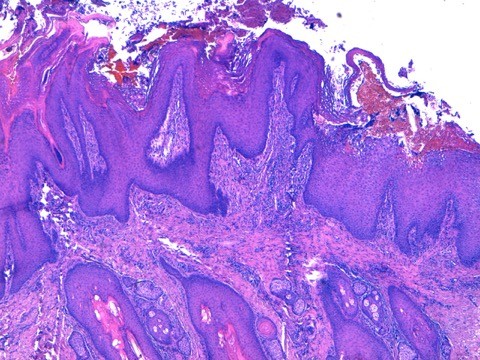

@ Biopsies (LAPVSO) : « Quatre biopsies cutanées sont examinées selon différents niveaux de section et après réaction au PAS.

L’épiderme apparaît multifocalement creusé de vésiculo-pustules relativement étendues. Elles peuvent se développer sous la couche cornée ou dans la couche granuleuse ou ponter plusieurs abouchements folliculaires contigus. Les squamo-croûtes ou les vésiculo-pustules contiennent des cellules épithéliales acidophiles, acantholysées, mêlées à des granulocytes neutrophiles ou éosinophiles et à des lamelles de kératine. Sur le plancher des vésiculo-pustules, constitué de l’épiderme et des infundibula folliculaires, on observe nettement un détachement, par plages, d’acanthocytes qui s’arrondissent, deviennent acidophiles, bombés, présentant encore un noyau viable. Le siège de ces pustules acantholytiques réside le plus souvent dans la couche granuleuse de l’épiderme ou au dessus dans la couche cornée. Le derme sous-jacent est paradoxalement peu inflammatoire. On y observe un infiltrat périvasculaire à diffus, exsudatif, relativement riche en cellules mastocytaires et en granulocytes éosinophiles, accompagnés de quelques lymphocytes. »

Photo 14 : histologie bord du coussinet, pustulose sous cornée

Aspect histologique d’une pustulose sous cornée granulocytaire acantholytique amicrobienne sans détection d’éléments figurés pathogènes ni parasitaires ni fongiques.

Aspect histologique orientant vers un pemphigus superficiel auto-immun ou éventuellement une éruption médicamenteuse mimant un pemphigus superficiel.